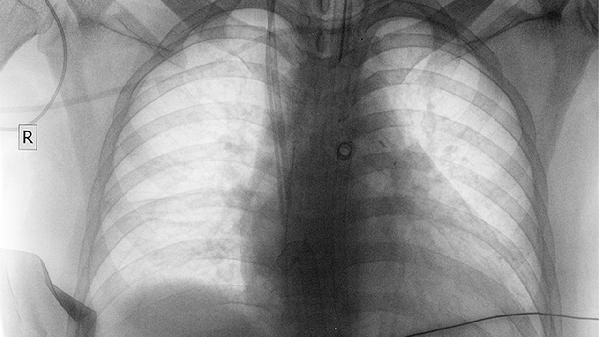

呼吸困难常在中晚期出现,表现为活动后气促或静息时呼吸费力。这与肿瘤阻塞大气道、导致肺不张或合并大量胸腔积液有关。呼吸困难程度可反映病情严重程度,需及时评估处理。